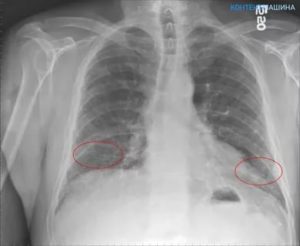

Для визуализации патологического процесса назначается рентгенологическое исследование органов грудной клетки, которое позволяет обнаружить изменения в легких. Обнаруживаются изменения с обеих сторон, преимущественно в нижних отделах легких.

Отмечаются усиление и деформация легочного рисунка, постепенно формируется картина так называемого «сотового легкого», которое характеризуется образованием кольцевых теней диаметром 3 – 7 мм со стенками толщиной до 3 мм, что в некоторой мере напоминает пчелиные соты.